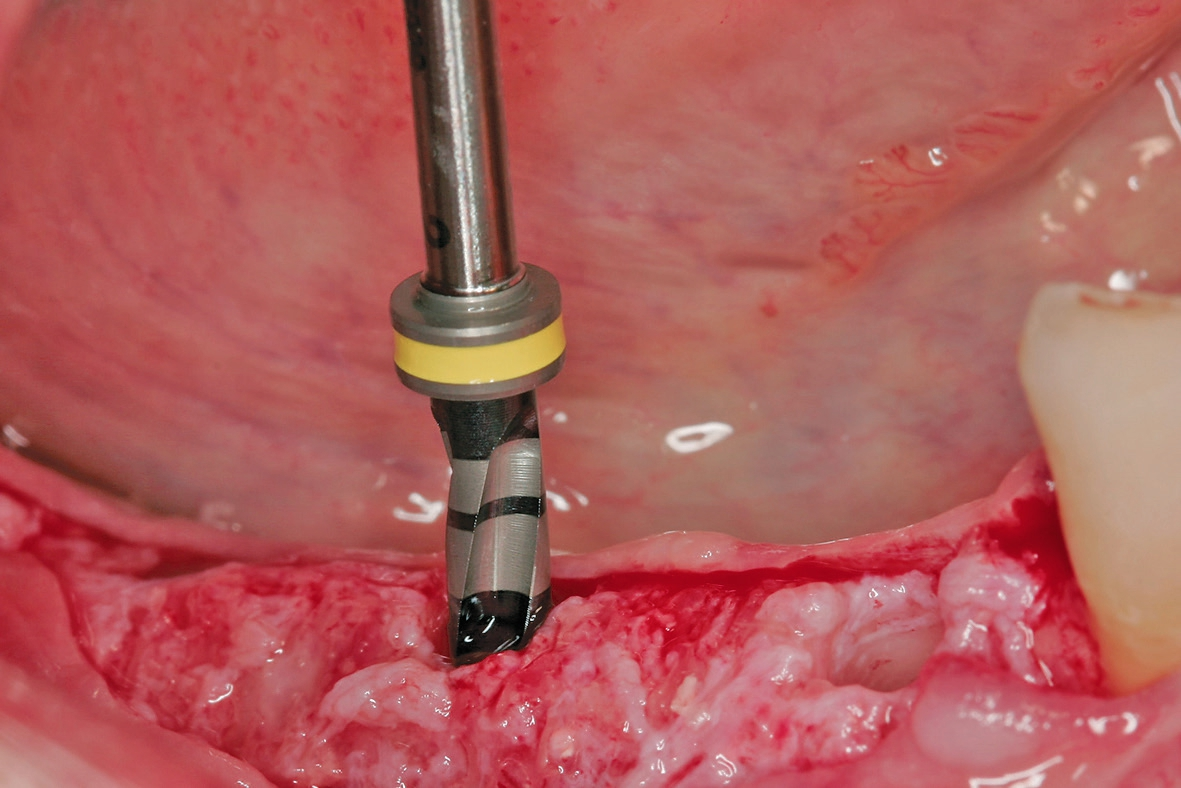

Der Lappen wurde reponiert und mit nicht resorbierbarem Nahtfaden der Stärke 4.0 adaptiert. Um einen spannungsfreien Wundverschluss zu erreichen, wurde apikal eine laterale Matratzennaht gesetzt. Die Nähte wurden nach 14 Tagen entfernt. Nach sechs Monaten komplikationsfreier Wund- und Einheilung kam die Patientin zur Implantatbehandlung erneut in die Praxis (Abb. 6 und 7). Beim Re-Entry wurden die Befestigungsschrauben entfernt, und es wurde eine Knochenkernbiopsie für die histologische Analyse entnommen (Abb. 8 und 9). Die histologische Untersuchung der mit Hämatoxylin-Eosin eingefärbten Schnittpräparate der Probe zeigte den laufenden Umbauprozess des FDBA-Blocks. Die histologische Aufnahme (Abb. 10) zeigte neu gebildeten Geflechtknochen (WB) in engem Kontakt mit dem Allograftmaterial (*) und umgeben von Bindegewebe (CT) und belegte die durch das Allograftmaterial vermittelte Knochenregeneration. Nach Bestimmung der geeigneten Implantatpositionen wurden in regio 47, 46 und 44 drei Bone Level Implantate Straumann® BLX Roxolid® SLActive ® mit einem Durchmesser von 4,5 mm und einer Länge von 10 mm gesetzt (Abb. 11 bis 14). Die Implantate wurden mit RB Verschlusskappen verschlossen, der Wundverschluss erfolgte mit Nahtmaterial der Stärke 4.0 (Abb. 15 und 16).

Mit den BLX Implantaten wurde eine optimale Primärstabilität erreicht. Die BLX Bohrer ermöglichen ein intermittierendes Bohren. So kann die Implantatbettpräparation an die unterschiedlichen knöchernen Situationen angepasst und eine gute Primärstabilität erreicht werden. Das BLX Implantat erweist sich in Fällen wie diesem, in denen der Knochen des Implantatbetts von unterschiedlicher Dichte und Qualität ist, als äußerst einfach in der Anwendung.